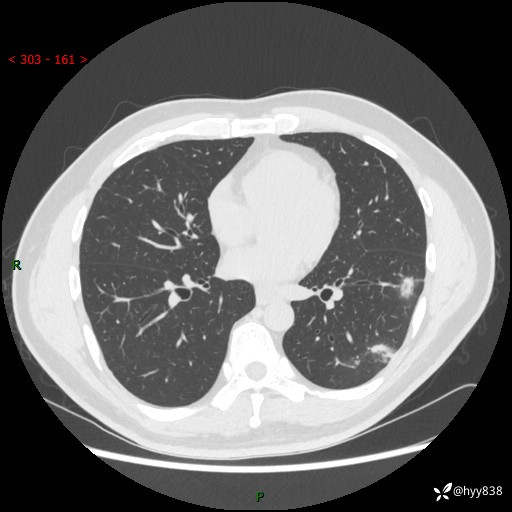

中年男性,胸闷3月余。多发团片、肺小叶分布、空气支气管征、明显强化---结果公布~

现病史:患者3月前出现胸闷,卧位时加重,坐位时缓解,无咽痛、咳嗽,无头痛,无全身酸痛,无结膜充血,无胸痛、心慌,无咯血,无呼吸困难,无咳痰,2024-07-02于当地市第一民医院行胸部CT,结果不详,2024-07-05就诊于我院急诊内科,行胸部CT同时增强,结果示:左肺下叶多发结节灶,考虑感染可能。今患者为求进一步诊治来我院,门诊以“肺部感染”收入我科。 患者本次起病来精神、食欲、睡眠尚可,大小便可,体力,体重无明显变化。

胸部CT平扫+增强

各期CT值:30hu 90hu 77hu